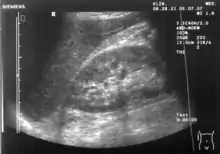

Renal ultrasonography

Ultrasound scan of a kidney (right side).

Ultrasonography of the kidneys is essential in the diagnosis and management of kidney-related diseases. The kidneys are easily examined, and most pathological changes in the kidneys are distinguishable with ultrasound.[7]